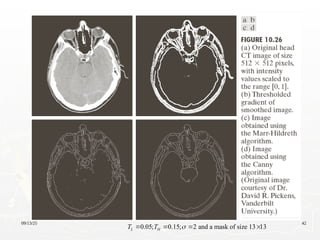

Marr-Hildreth Algorithm

1. Filter the input image with an nxn Gaussian lowpass

filter. N is the smallest odd integer greater than or

equal to 6

2. Compute the Laplacian of the image resulting from

step1

3. Find the zero crossing of the image from step 2

 

2

( , ) ( , ) ( , )

g x y G x y f x y

The Canny Edge Detector

► Optimal for step edges corrupted by white noise.

0.04; 0.10; 4 and a mask of size 25 25

L H

T T 

   

09/13/25 42

0.05; 0.15; 2 and a mask of size 13 13